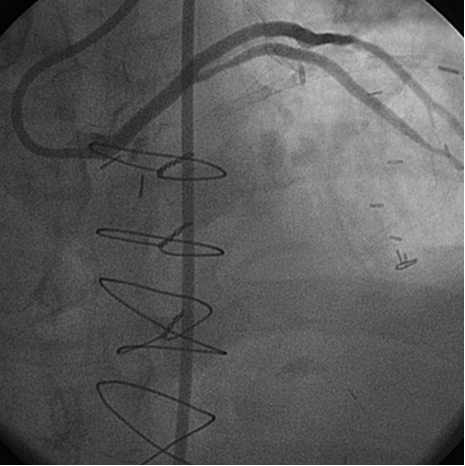

The most commonly used catheters for left heart catheterization and vein graft angiography can be seen in Figure 1 and Figure 4-13. Most of the vein grafts have horizontal take off and can be successfully engaged using a commonly used Judkins right number 4 (JR4) catheter. The JR4 catheter is the most commonly used catheter for the engagement of the right coronary ostium with horizontal take off. However, many vein grafts have unusual take off requiring different catheters. Many right coronary vein grafts have steep inferior take off making the ostial engagement with JR4 difficult or impossible (Figure 10). In such a scenario, a multipurpose catheter which has a shallow angulation is the best choice (Figure 11). The second major challenge in engaging vein graft ostia, particularly vein grafts supplying the left coronary arteries, is the shape of the aorta. A large aorta can make it very difficult for the JR4 catheter to reach the ostial vein grafts. In such a situation, Amplatz (AR) right and left (AL) catheters can be very helpful to reach the vein graft ostia. Amplatz catheters have a larger primary curve and have been used successfully in unusual superior take off of left coronary arteries or vein grafts and in large aorta. Amplatz catheters are available in different sizes (from smaller to larger curve: AR 1, AR2, AL2, AL2 and AL3). Occasionally, a very superior take off of a vein graft requires specially designed bypass graft catheters. Amplatz catheters are also extremely helpful in engaging native right coronary ostium with anterior take off.

PCI of the vein and arterial grafts have unique challenges. For any PCI, guide support is very important for successful balloon and stent delivery. In a tortuous vein graft with a steep angle, advancement of a stent can be very difficult and challenging. Therefore, it is important to choose the best available catheter before starting PCI. Similar to the right coronary angiography, a JR4 guide catheter is most commonly used in this setting. However, Amplatz guide catheters for left vein grafts and multipurpose catheters for right vein grafts are better choices in certain anatomy. In Figure 8 and Figure 10 two examples of poor guide support in two vein graft interventions can be seen. Initially, a JR4 guide was used for PCI of the vein graft supplying the left anterior descending artery (LAD) without any success. However, after changing the guide to an Amplatz left 2 guide catheter, we achieved excellent support without any difficulty in advancing two stents (Figure 9). In Figure 10, difficulty is illustrated in engaging the vein graft ostium supplying the right coronary artery with a JR4 catheter. This vein graft has a very steep inferior take off from the aorta. After changing the guide to a multipurpose catheter, we were able to deliver three stents successfully without any difficulties (Figure 11). Similar challenges exist in the treatment of the left IMA or right IMA. These arterial grafts can be extremely tortuous making stent delivery very difficult. It may be necessary to use short length stents for a better deliverability or stents with lowest profile. Usually, similar to the native coronary intervention, a 6 French guide is appropriate for the routine use.